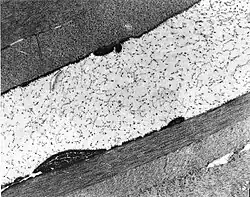

Congenital stromal dystrophy. Transmission electron microscopy of the corneal stroma showing normal collagen lamellae separated by abnormal randomly distributed collagen filaments in an electron-lucent extracellular matrix.

Congenital stromal corneal dystrophy (CSCD) is an extremely rare, autosomal dominant form of corneal dystrophy.[1] Only 4 families have been reported to have the disease by 2009.[2] The main features of the disease are numerous opaque flaky or feathery areas of clouding in the stroma that multiply with age and eventually preclude visibility of the endothelium. Strabismus or primary open angle glaucoma was noted in some of the patients. Thickness of the cornea stays the same, Descemet's membrane and endothelium are relatively unaffected, but the fibrils of collagen that constitute stromal lamellae are reduced in diameter and lamellae themselves are packed significantly more tightly.